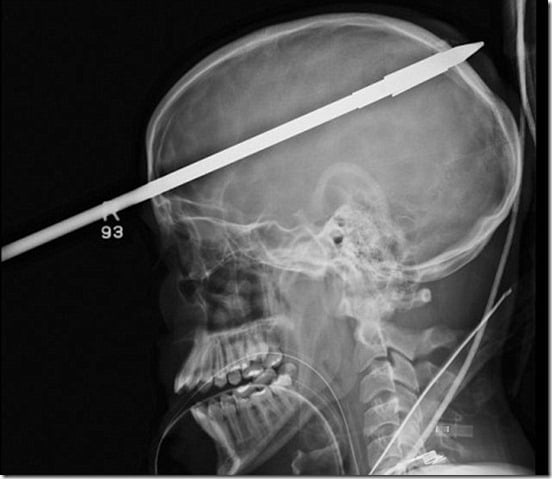

Um garoto de 16 anos Yasser Lopez de alguma forma conseguiu sobreviver a uma lança de 3 metros que entrou em sua cabeça.

O acidente aconteceu quando um arpão foi disparado por engano ao ser carregado, a lança maciça entrou através de seu cérebro com a extremidade saliente chegando a traseira de seu crânio.

Milagrosamente, Lopez não foi morto -. a lança não atingiu os grandes vasos sanguíneos em seu cérebro "É um milagre a lança perdeu todos os principais vasos sanguíneos do cérebro", disse o neurocirurgião Ross Bullock.